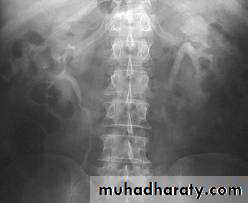

-Over 90% of calculi are radiopaque on plain films and virtually all on CT as very sensitive for detection of calculi, even those that appear radiolucent on plain film.

-Principal feature is dilatation of the pelvicalyceal system and ureter.

• The dilatation is down to the level of pathology

l.V.U. findings:

-Plain film may be useful in demonstrating calculi.

-After contrast injection:

Acutely obstructed kidney shows a dense nephrogram (dense opacification of the renal parenchyma).

excretion of contrast (opacification of the collecting system which may take many hours), then the level and degree of obstruction can be determined as dilated pelvi-caliceal system and ureter are followed down to the point of obstruction (point of hold up).

Pyeloxinus reflux may result from rupture of a fornix precipitated by contrast-induced diuresis superimposed on the increased hydrostatic pressure of an obstructed pelvicaliceal system. Urine and contrast extravasate into the renal sinus and perirenal space